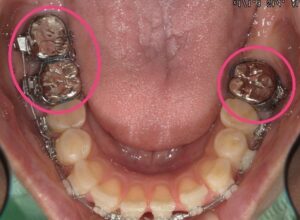

● バンド

主に第一大臼歯(6番)につけるリング状の装置。外れにくく、強い固定源になる。

⑤ 矯正の経過写真

矯正開始前と最新のお写真を掲載しています。

実際の変化が伝わりやすいので、ぜひご覧ください。

治療途中(現在)